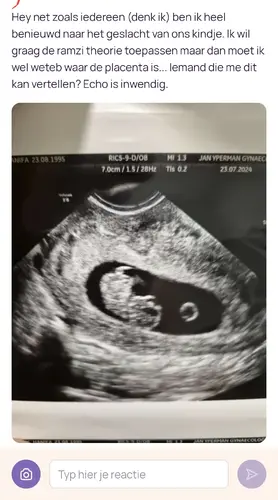

Heb je kunnen vragen aan je gynecoloog waar de placenta ligt? Volgens ramzi theorie

Op Inwendige echo: links meisje rechts een jongen

Op Uitwendig omgekeerd.

Als ik me goed begrijp he natuurlijk..😅😅

Of je kan anders ramzi theorie opzoeken?😁 Laat mij weten als je een antwoord hebt 😉😉

Volgens de foto en de ramzi theorie denk ik en ik ga mijn mening veranderen. Dus de baby zal een jongen zijn? 😅😅